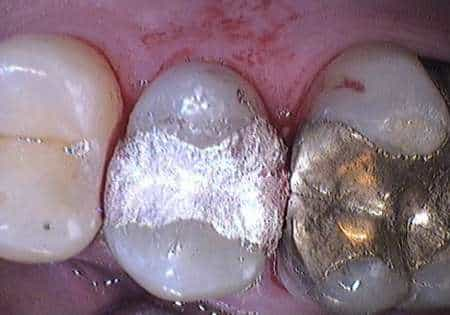

La Food and Drug Administration, l’agenzia statunitense che regolamenta i farmaci e gli ausili terapeutici, ha finalmente riclassificato l’amalgama dentale, il materiale usato per le otturazioni odontoiatriche che è da sempre oggetto di controversia perché composto per il 50 % da mercurio elementare, una sostanza potenzialmente tossica, e per il restante 50% da altri metalli in forma di polvere, soprattutto argento, rame e stagno. La FDA è stata costretta a concludere il suo processo di valutazione dell’amalgama dentale da una sentenza del tribunale civile del giugno 2008 che dava ragione alla richiesta presentata da un gruppo di associazioni di consumatori e di vittime dell’amalgama, tra cui Moms Against Mercury, Connecticut Coalition for Environmental Justice, Oregonians for Life e Consumers for Dental Choice. Queste avevano chiesto una riclassificazione sin dal 1993 e pretendevano che la FDA stringesse i tempi di classificazione dell’amalgama, soprattutto in considerazione delle crescenti evidenze scientifiche di potenziali danni per la salute. L’amalgama dentale, infatti, essendo un materiale messo in commercio sin dall’Ottocento, era in uso prima del 28 maggio 1976, quando alla FDA era stato dato ampio potere di regolamentare i dispositivi medici. Da allora c’era una classificazione delle due componenti separate dell’amalgama (ovvero il mercurio elementare e la polvere dei vari metalli) ma non della loro combinazione. Dopo una revisione di 200 studi recenti sulla tossicità dell’amalgama e dei materiali che la compongono, la FDA ha concluso che questo materiale non è tossico e che i vapori rilasciati dalle otturazioni non sono tali da comportare un pericolo per la salute. Tuttavia, questo materiale passa dalla Classe I, che indica un “rischio basso”, alla Classe II che indica un “rischio moderato”. La nuova classificazione consente alla FDA di imporre controlli speciali oltre a quelli generali sui processi di fabbricazione che si applicano a tutti i dispositivi medici. «Siamo piuttosto sconcertati da questa conclusione – commenta Francesca Romana Orlando, Vice Presidente di A.M.I.C.A. – dato che, già nel settembre 2006, il documento preparato dalla Divisione di Odontoiatria della FDA, che aveva concluso che le amalgame erano sicure, era stato bocciato dalla commissione di esperti indipendenti con 13 voti a sfavore contro 7 favorevoli». La stessa FDA aveva raggiunto un accordo con le associazioni di pazienti e di consumatori, nell’ambito della sentenza del giugno 2008, e aveva pubblicato sul suo sito una informativa più cauta, cioè che “le amalgame possono avere effetti neurotossici sul sistema nervoso di bambini in via di sviluppo e nei feti” e che “donne in cinta e soggetti che potrebbero avere condizioni di salute che li rende più sensibili all’esposizione al mercurio, compresi coloro con pre-esistente carico tossico da mercurio, dovrebbero discutere con il proprio medico delle alternative (alle amalgame)”. “Questi avvertimenti non sono presenti negli obblighi della etichettatura delle amalgame – prosegue la dott.ssa Orlando – e rimane solo il riconoscimento dei rischi per gli allergici e l’obbligo per i dentisti di avvertire i propri pazienti riguardo la presenza del mercurio in questo materiale dentale”. «Questa classificazione per noi, così come per le altre associazioni statunitensi e spagnole6 con cui collaboriamo, è insufficiente perché non tiene conto di numerosi aspetti scientifici: innanzitutto della inadeguatezza degli studi basati sul test delle urine usato per stabilire gli effetti della esposizione a vapori di mercurio o della esposizione ai metalli dell’amalgama. Diversi esperimenti su pecore e scimmie, infatti, hanno mostrato che la maggior parte del mercurio contenuto nelle amalgame dentali viene assorbito dai reni, dal fegato, dal cervello e dalle ossa della mandibola e della mascella dove, secondo molti scienziati, possono interferire con le attività neurologiche e del sistema immunitario; in secondo luogo, il test delle urine, usato spesso dagli studi che tranquillizzano sulla non tossicità delle amalgame, potrebbe non essere indicativo perché la minore presenza di mercurio nelle urine potrebbe essere causata da una scarsa capacità di metabolizzazione (espulsione) di questa tossina7 e, quindi, paradossalmente, livelli più bassi di mercurio nelle urine potrebbero indicare uno stato di tossicità e non uno stato di salute. A sostenerlo è da anni sostiene uno dei maggiori esperti di biochimica, il prof. Boyd Haley, Direttore del dipartimento di Chimica dell’Università del Kentucky, USA». Con la classificazione di oggi la FDA raccomanda la presenza di precise indicazioni sull’etichettatura delle amalgame dentali: